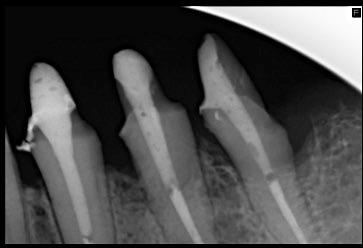

Ebben a cikkben egy 16 éves lánypáciens esetét szeretném bemutatni (1–7. képek)

A Pitts21-es fix készülékes kezelés során a harapásemelőket a felső nagyőrlő fogakra ragasztottuk, hogy a felső molárisok intrúziójával segítsék a harapás zárását (8. kép) Ún. keresztharapásos, majd később normál class 2-es gumihúzással (9–10. képek), továbbá az elülső fogakon alkalmazott ún. Rainbow harapás-záró gumihúzással (11. kép) korrigáltuk a jobb oldali teljes premolárisnyi distal-harapást, valamint az elülső nyitott harapást.